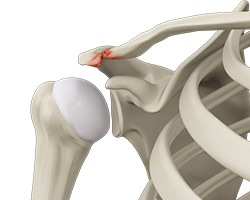

What is AC or Acromioclavicular Arthritis?

The acromioclavicular joint is part of the shoulder joint. It is formed by the union of the acromion, a bony process of the shoulder blade, and the outer end of the collar bone or clavicle. The joint is lined by cartilage that gradually wears with age as well as with repeated overhead or shoulder level activities such as basketball. The condition is referred to as AC arthritis or acromioclavicular arthritis.